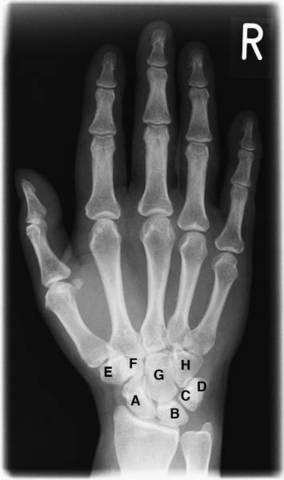

Bertan "argiririk" duen frogatuko dute, hala ez bada duen adina frogatuko dute, "hezur frogaren bidez, karpoaren erradiografia (osasun zetroan) burutuko dute. Profesionalek 16 urte dituela uste dute, frogan ez da zehaztu adin finkoa, hortaz 16-18 urte izango dituela pentstauko dute. Bere babesgabetasuna bermatzeko asmoz, adin txikiena artuko dute kontutan.